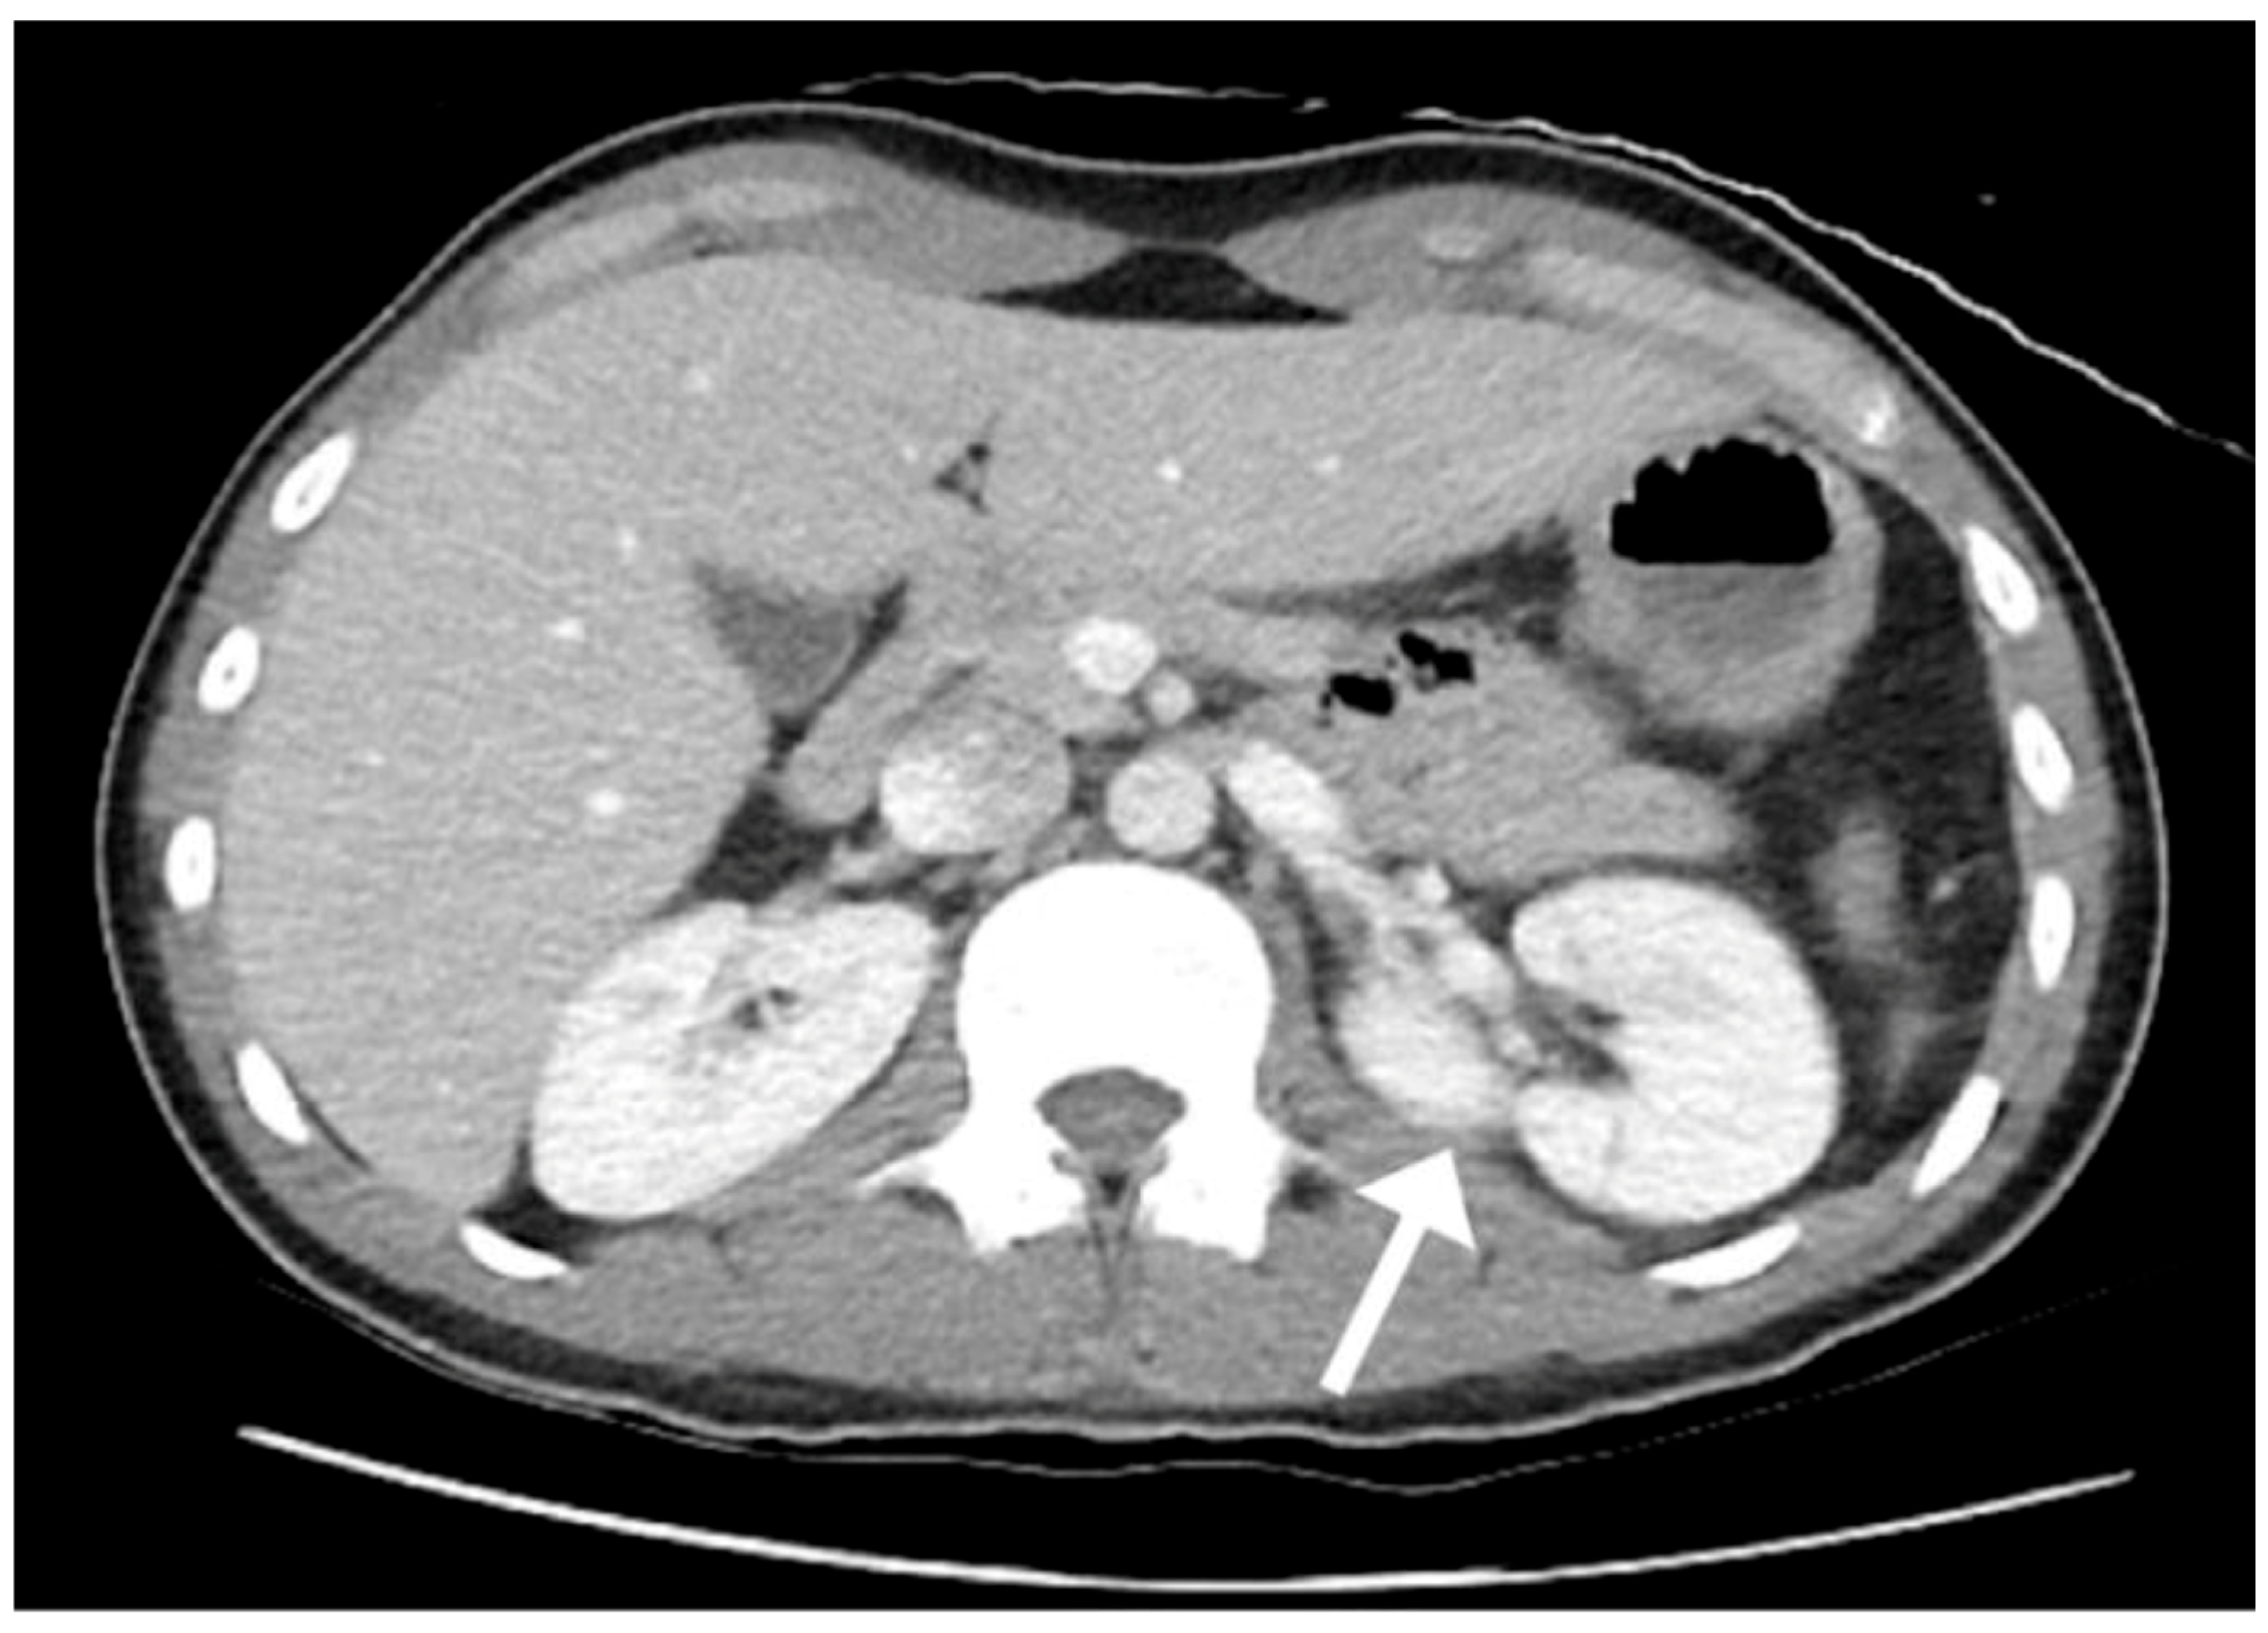

2. Case Presentation